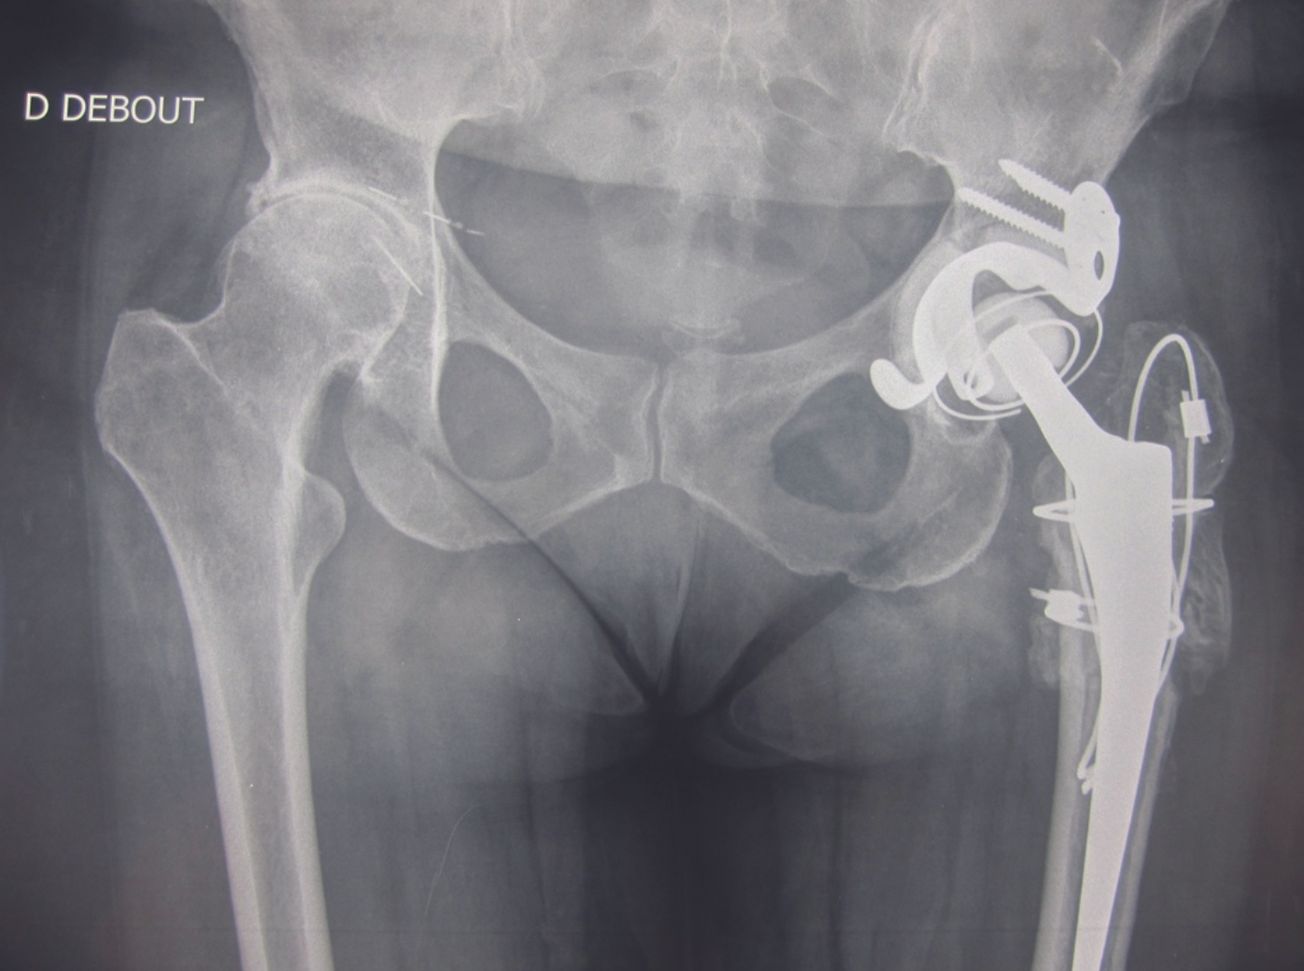

Technique Reconstruction du cotyle dans les reprises de PTH par Double Cupule et Ingénierie Tissulaire Osseuse , Christophe Trojani Service de Chirurgie Orthopédique et Traumatologie du Sport - Hôpital de l’Archet 2 - CHU de Nice, Nice, France , Jean-Luc Raynier Institut de Chirurgie Réparatrice Locomoteur et de Sport (ICR) ; Clinique Kantys Centre, Groupe Kantys, 7 av Durante, 06 Nice , Vincent Lavoué Institut de Chirurgie Réparatrice Locomoteur et de Sport (ICR) ; Clinique Kantys Centre, Groupe Kantys, 7 av Durante, 06 Nice , Gilles Clowez Institut de Chirurgie Réparatrice Locomoteur et de Sport (ICR) ; Clinique Kantys Centre, Groupe Kantys, 7 av Durante, 06 Nice , Pascal Boileau Service de Chirurgie Orthopédique et Traumatologie du Sport, Hôpital de l’Archet 2, Université de Nice, Nice, France 🖂 boileau.p@chu-nice.fr N°312 - Mars 2022 ● 16 min de lecture